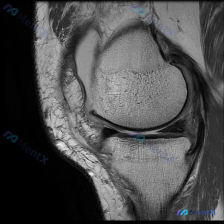

病例影像读片分享 整理了这张单膝关节冠状位T2加权脂肪抑制MRI,跟大家分享一下读片思路 影像基本信息 这是一张膝关节冠状位T2加权脂肪抑制序列MRI,图像对比度良好,能够清晰显示关节内软组织结构;左侧为膝关节外侧,右侧为内侧,本次显示层面包含股骨外侧髁、胫骨外侧平台及外侧关节间隙。 影像观察结果...